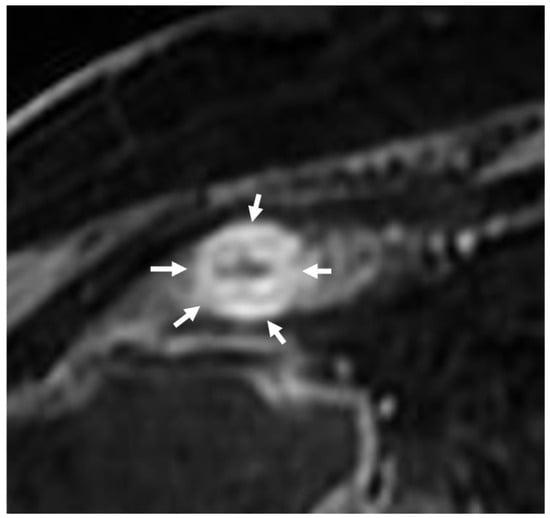

6. Is the Stricture Fibrotic or Inflammatory?

- Foti, P.V.; Travali, M.; Farina, R.; Palmucci, S.; Coronella, M.; Spatola, C.; Puzzo, L.; Garro, R.; Inserra, G.; Riguccio, G.; et al. Can Conventional and Diffusion-Weighted MR Enterography Biomarkers Differentiate Inflammatory from Fibrotic Strictures in Crohn’s Disease? Medicina 2021, 57, 265. [Google Scholar] [CrossRef]

- Du, J.F.; Lu, B.L.; Huang, S.Y.; Mao, R.; Zhang, Z.W.; Cao, Q.H.; Chen, Z.H.; Li, S.Y.; Qin, Q.L.; Sun, C.H.; et al. A novel identification system combining diffusion kurtosis imaging with conventional magnetic resonance imaging to assess intestinal strictures in patients with Crohn’s disease. Abdom. Radiol. 2021, 46, 936–947. [Google Scholar] [CrossRef] [PubMed]

- Fang, Z.N.; Li, X.H.; Lin, J.J.; Huang, S.Y.; Cao, Q.H.; Chen, Z.H.; Sun, C.H.; Zhang, Z.W.; Rieder, F.; Rimola, J.; et al. Magnetisation transfer imaging adds information to conventional MRIs to differentiate inflammatory from fibrotic components of small intestinal strictures in Crohn’s disease. Eur. Radiol. 2020, 30, 1938–1947. [Google Scholar] [CrossRef] [PubMed]

- Zhong, Y.K.; Lu, B.L.; Huang, S.Y.; Chen, Y.J.; Li, Z.P.; Rimola, J. Cross-sectional imaging for assessing intestinal fibrosis in Crohn’s disease. J. Dig. Dis. 2020, 21, 342–350. [Google Scholar] [CrossRef]